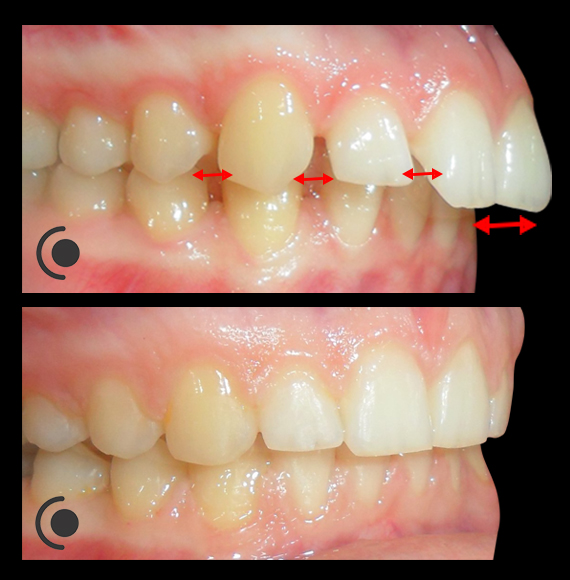

O našoj kvaliteti najbolje govore naši rezultati!

Centar za ortodonciju Petra Džapo